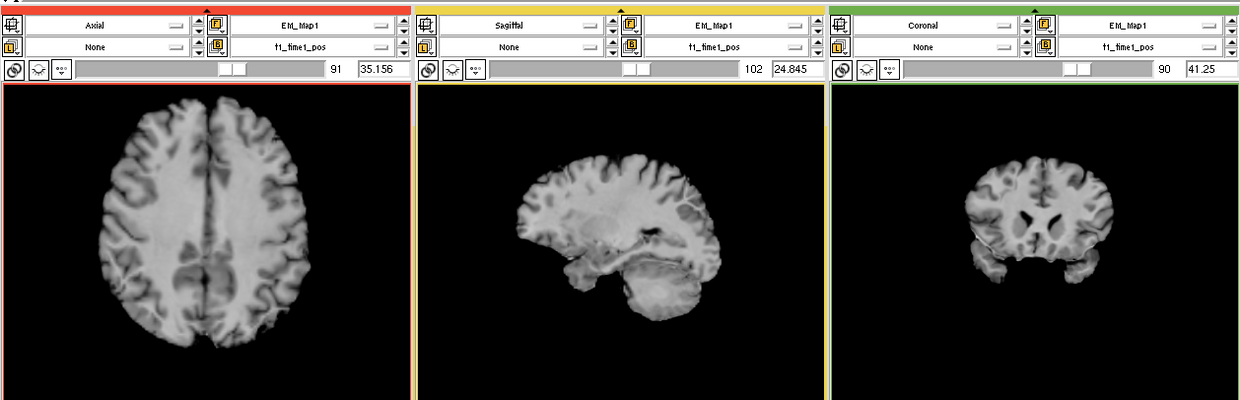

The goal is to segment white matter lesions based on T1 and FLAIR brain scans.

We want to use the EMSegmenter module for this project. The plan is to create a two channel pipeline which includes pre-processing (e.g. registration) and applying the EM algorithm to perform the segmentation.

We created a 2 channnel(T1+FLAIR) pipeline for this project. Intensity values of the lesions are calculated automatic but have to manually updated to get a better result. (see segmentation screenshot)